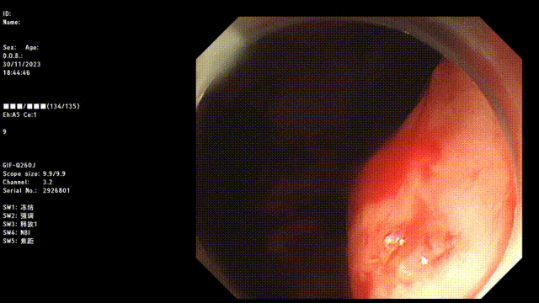

image.png

止血成功